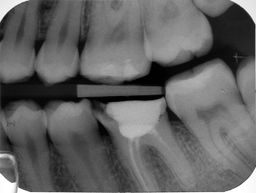

Farbkodierte Guttaperchastifte unterschiedlicher Größen stecken als Wurzelfüllung in den Kanälen.

Nach abgeschlossener Wurzelkanalbehandlung wird der Zugang sofort dicht verschlossen – hier mit Amalgam. Ein dichter Koronalverschluss ist entscheidend für den Langzeiterfolg der Wurzelkanalbehandlung.